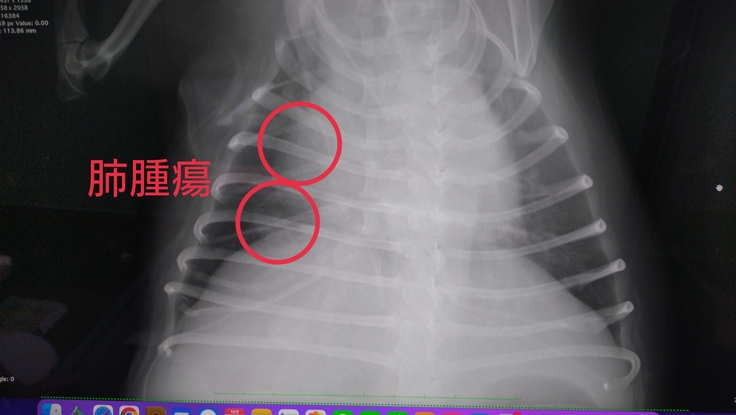

肺に転移はほぼ確定…影あり。角度によっては見えないけど、、、